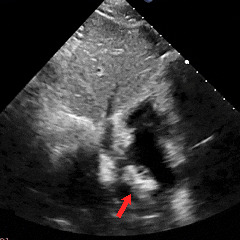

冠状动脉CTA:冠状动脉分布呈均衡型,左前降支中段浅肌桥;余冠状动脉CTA未见明显异常;卵圆孔未闭;左房囊袋。

冠脉CTA(长隧道+大开口+左房囊袋PFO)